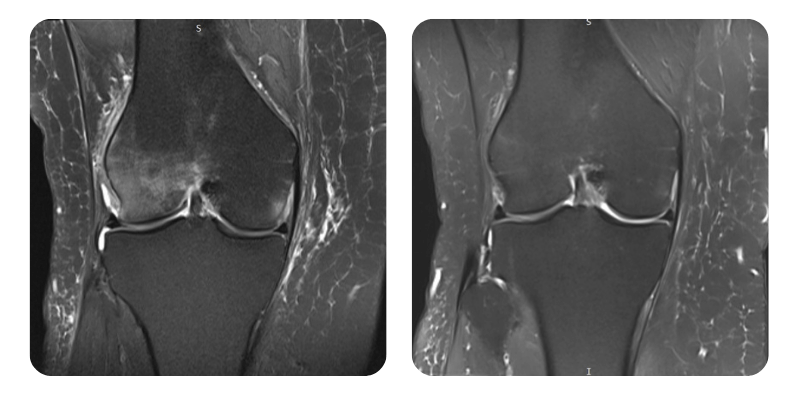

Before

After

S.M.S., 58 years old - Necrosis/Edema of the right lateral femoral condyle

Evolution: MRI shows an approximate 90% reduction in edema.